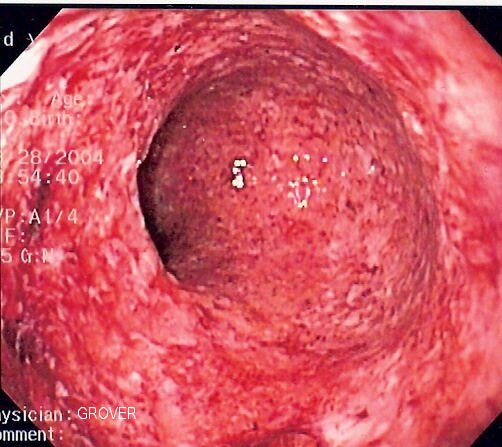

Kolonoskopia

Kolonoskopia jest ważnym badaniem wykonywanym w profilaktyce raka jelita grubego. Polega na wprowadzeniu przez odbyt giętkiego przyrządu zakończonego kamerą (kolonoskopu). Umożliwia to obserwację ścian i pobieranie wycinków błony śluzowej jelita grubego do badań histopatologicznych, a także wykonywanie drobnych zabiegów, jak np. usunięcie polipów, lub ostrzyknięcie środkami hamującymi krwawienie.